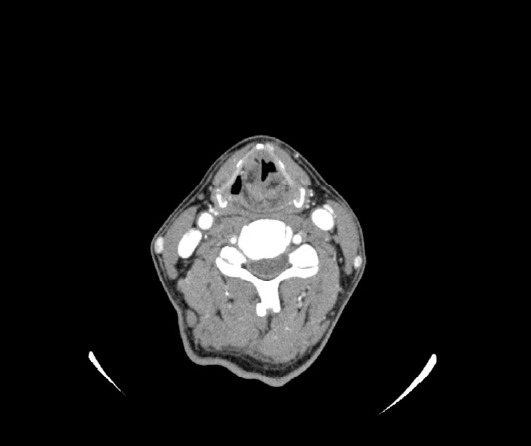

A 51-year-old man with a 10-day history of acute-onset dysphagia presented with inability to swallow anything orally. The patient was unable to swallow any radiopaque contrast medium; therefore, a videofluoroscopic swallow study could not be performed. Brain imaging, neurological findings, and initial endoscopy findings were normal. Neck computed tomography suggested left vocal cord paralysis. The patient was diagnosed with diabetes one year prior to presentation but did not receive any treatment. Insulin therapy during hospitalization controlled the patient's blood glucose levels, and his symptoms improved without any sequelae. We present a rare case of vocal cord paralysis secondary to controlled diabetes. The initial endoscopic examination did not include thorough evaluation of the vocal cords; therefore, accurate diagnosis was challenging in this case.

一名51岁男性,有10天急性发作吞咽困难病史,表现为无法口服任何东西。患者无法吞咽任何不透射线的造影剂;因此,无法进行视频透视吞咽研究。脑成像、神经系统检查结果和初步内窥镜检查结果均正常。颈部计算机断层扫描显示左声带麻痹。患者在就诊前一年被诊断为糖尿病,但未接受任何治疗。住院期间的胰岛素治疗控制了患者的血糖水平,症状得到改善,没有任何后遗症。我们报告了一例罕见的继发于控制性糖尿病的声带麻痹病例。最初的内窥镜检查不包括对声带的彻底评估;因此,在这种情况下,准确的诊断具有挑战性。